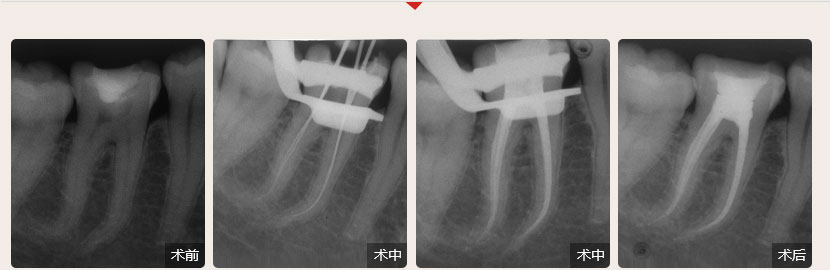

德倫口腔醫生全國根管治療技術競賽獲獎案例展示

根管治療過程